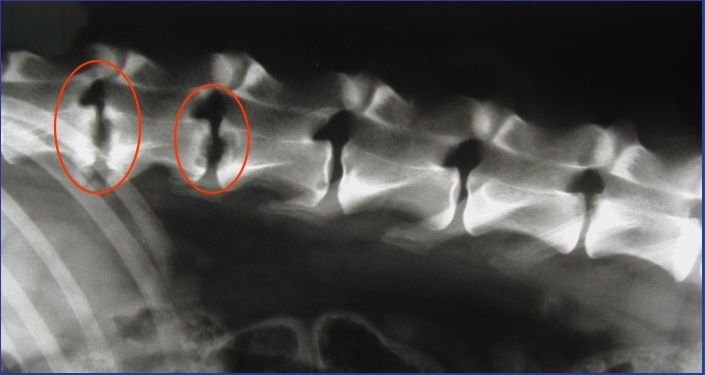

Radiographs (X-rays) of the spine will typically show damage to the vertebrae on either side of the affected discs. In chronic cases, bone changes and deformities of the spine may be seen. Changes may not show up on the radiographs for 3-6 weeks after clinical signs start, so if the first radiographs are normal but the clinical signs are progressing, your veterinarian will likely repeat the radiographs.

If a typical lesion is detected, radiographs of the entire spine are recommended because some pets have multiple lesions. Infection causes disc degeneration and destroys the ends of the adjacent vertebrae. These degenerative changes may weaken the vertebral column and make it susceptible to pathologic fractures, which stem from infection rather than trauma. The body may try to bridge the damaged area with bone, which can encroach on the spinal cord and nerve roots, causing more problems.